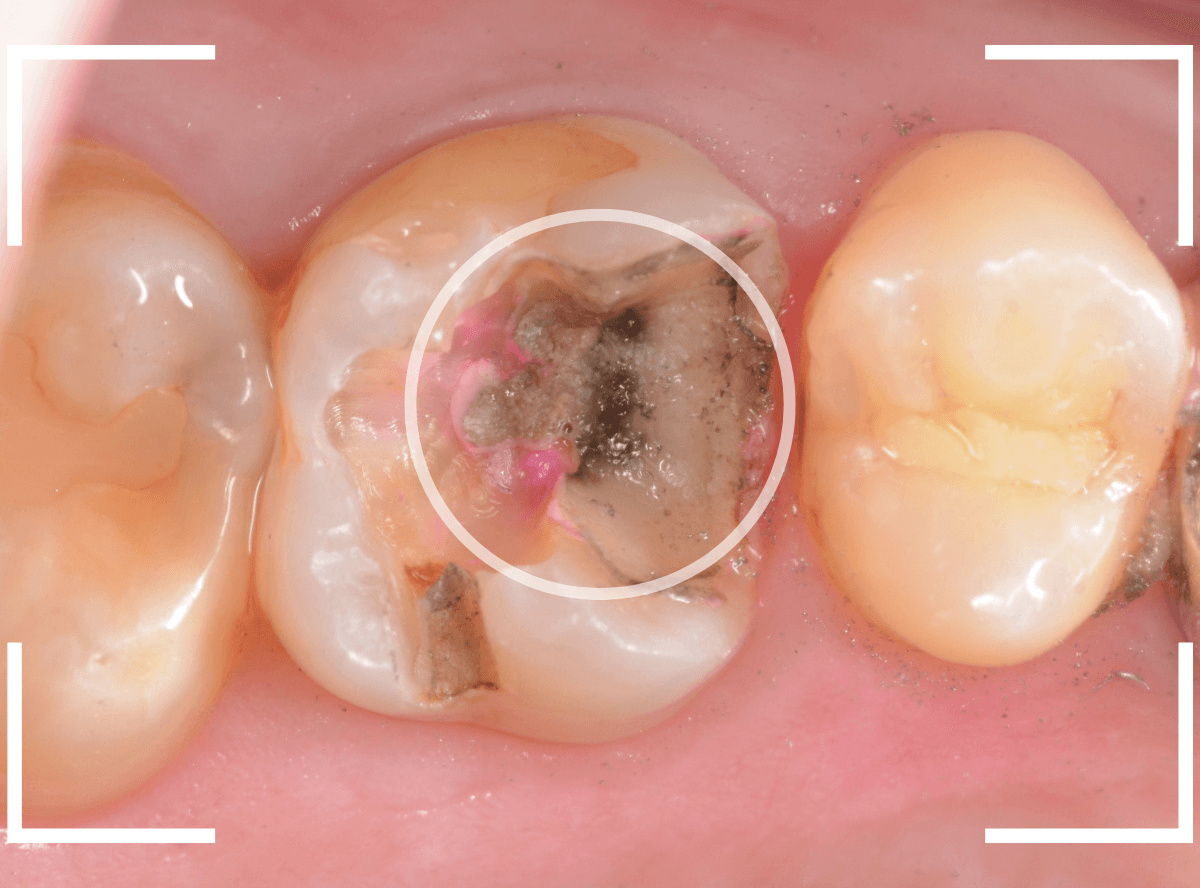

Case.12 検診で見つかった、インレーの下の深い虫歯

検診目的で来院された患者さんです。

特に気になるところもなかったですが、検査をすると、お口の中の色々な部分に虫歯が見つかりました。

その中の一か所、上の奥歯のインレーの下の虫歯です。

見た目だけでははっきりわかりませんでしたが、レントゲン写真で確認すると、インレーの下で虫歯になっているのがわかります。

インレーを除去して、治療を開始します。

ある程度、虫歯を除去したところで、う蝕検知液で確認します。

赤い部分が虫歯です。

やはり、レントゲン写真で確認した部分が深めの虫歯になっていたようです。

全ての虫歯を除去しました。

お薬をつめて痛みやしみが出ないか、しばらく経過観察しますが、おそらく大丈夫でしょう。

症状が出る前に、検診に来ていただいたことで最小限の治療で済みました。